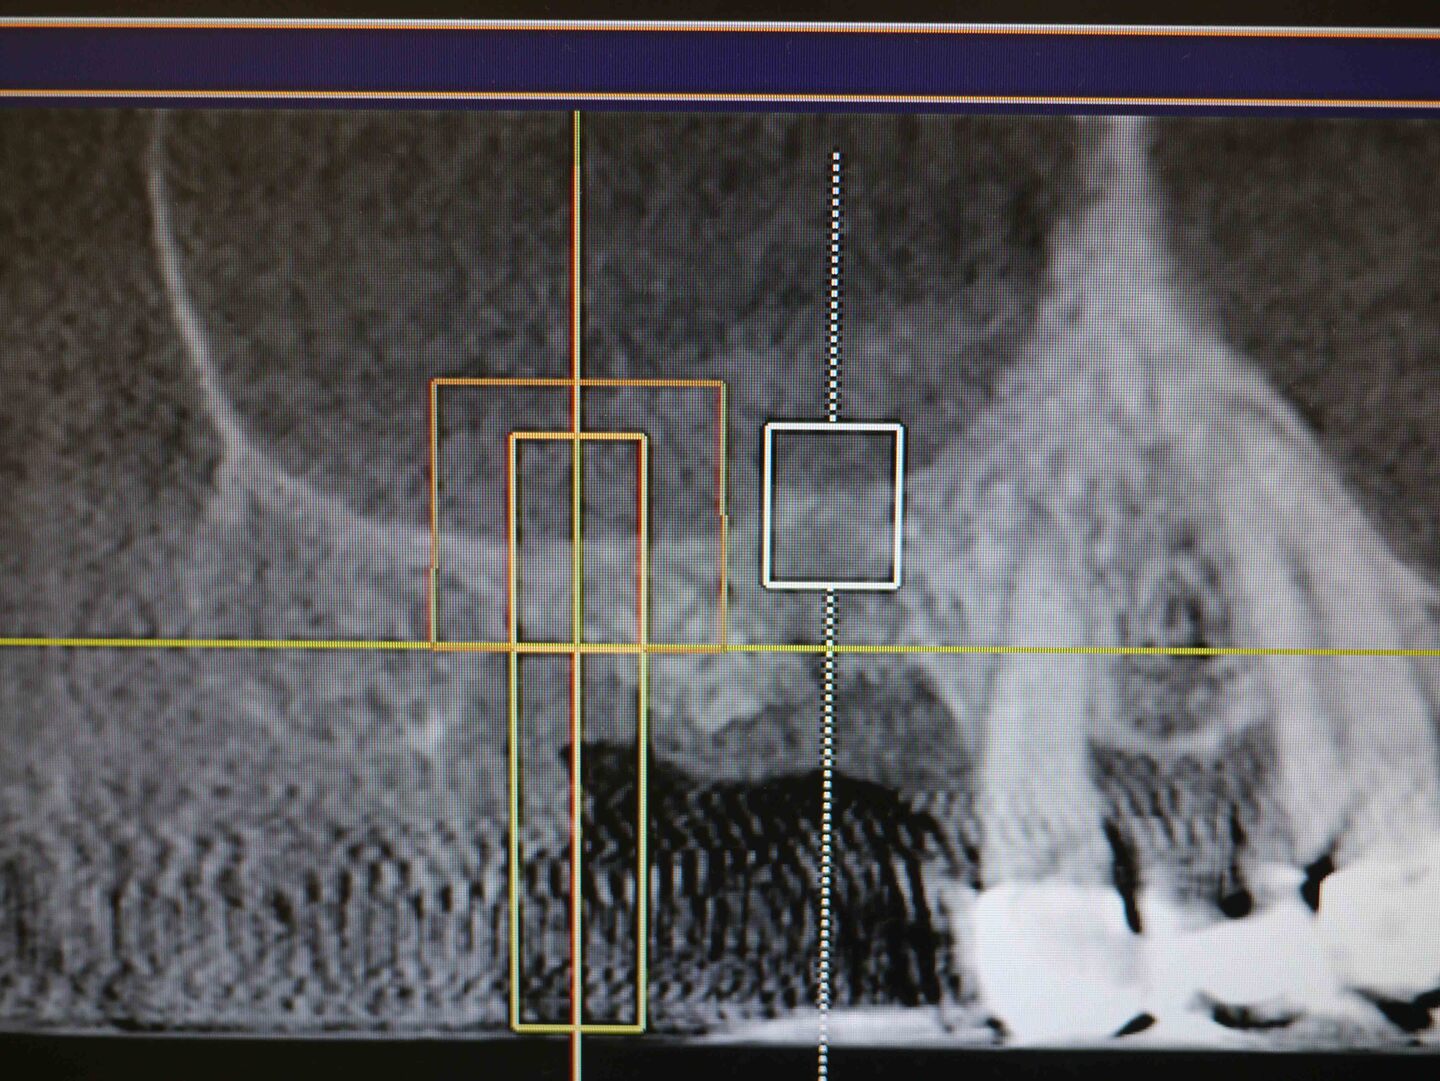

CT画像 2

右上7番埋入予定の骨を後側から見たCT画像